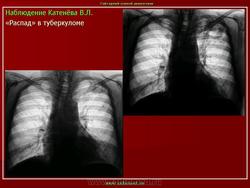

1. Множственные туберкулемы с распадом. В верхней доле правого легкого расположены множественные округлые тени, диаметром 1.5-2 см. средней интенсивности, с просветлением в центре, с четкими контурами.

2. Туберкулема в фазе распада. На томограммах в верхней долях правого и левого легкого определяются округлые тени, с четкими контурами, размерами 6 х 7 см. средней интенсивности, с просветлениями внутри.

Наблюдение Катенёва В.Л.